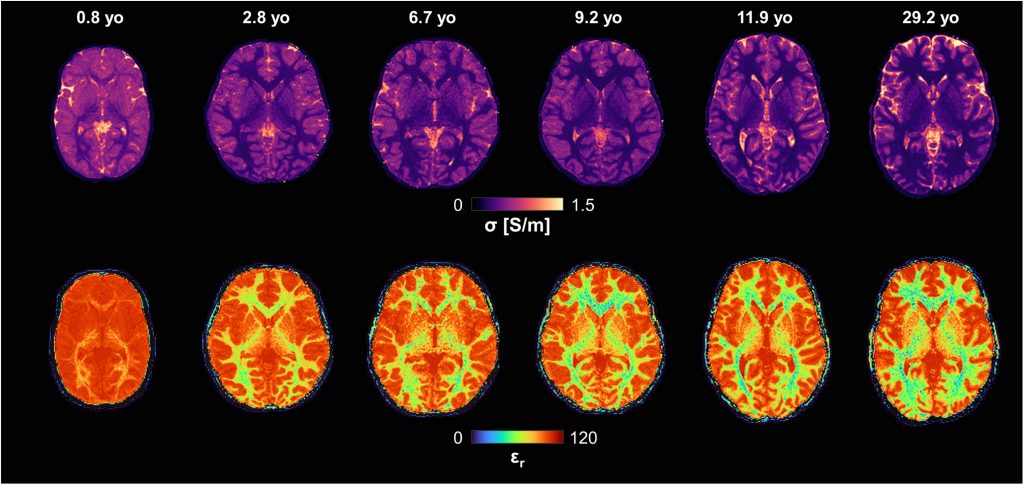

Marmin S, Arduino A, Cencini M, Lancione M, Biagi L, Tosetti M, Zilberti L

Linking dielectric dispersion and age in brain tissues via water content-based Electric Properties Tomography

NeuroImage, 322, 121559, 2025

ABSTRACT: Popular dielectric dispersion models of biological tissues, which describe dielectric properties as a function of frequency, do not account for age-related variations. In particular, existing databases have limited validity in pediatric populations. In this work, we applied water content-based Electric Properties Tomography in vivo to healthy subjects across the lifespan to incorporate age-related information into dielectric dispersion models of white and grey matter. Water content, derived from magnetic resonance fingerprinting-based mapping, was modelled as a function of age. The age-water relationships was then integrated with Cole-Cole dispersion via water-dependent permittivity and conductivity equations. The resulting model allows obtaining age-specific conductivity and permittivity of brain tissues at frequencies higher than 50 MHz. In addition, it provides confidence intervals accounting for both intra-subject and inter-subject variability. In terms of applications for brain studies, this model enables age-specific electromagnetic simulations for pediatric subjects and evaluations on the safety of electromagnetic exposure in developing brains. An open code is freely available online to compute electrical properties and their uncertainties as a function of frequency and age.